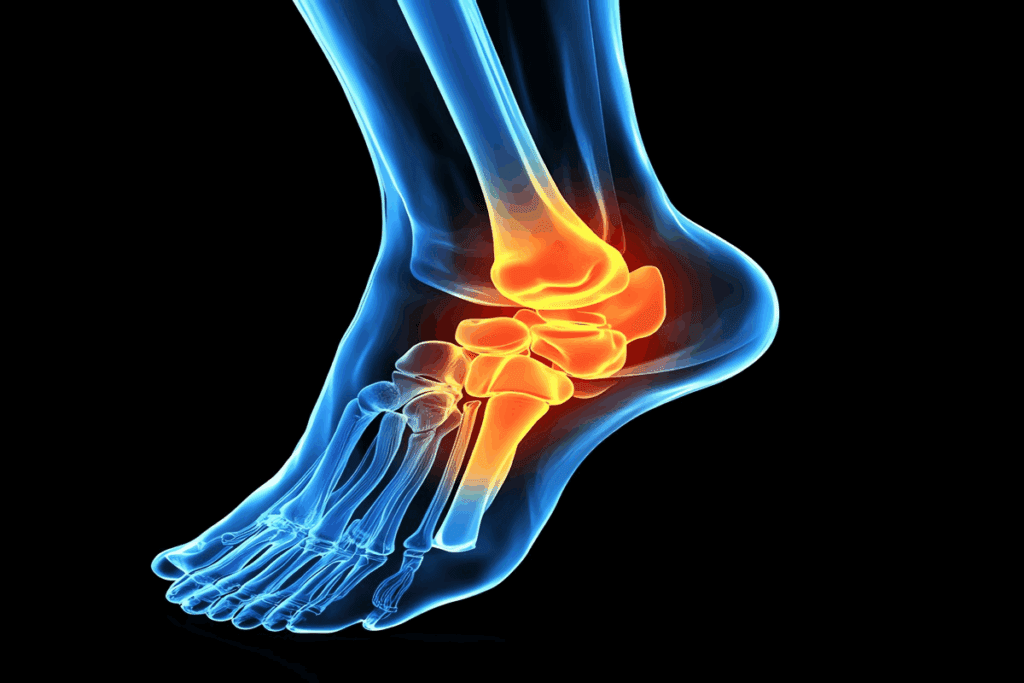

Common Locations for Tendonitis in the Body

Tendonitis can happen in many places, but it’s most common where there’s a lot of stress or strain. You often see it in the shoulders, elbows, wrists, hips, knees, and ankles.

Lower Extremity Tendonitis Diagnosis

Lower body tendonitis, like in the hip, knee, or ankle, has its own challenges. For example, Achilles tendonitis needs a detailed look at the tendon sheath and nearby tissues.

| Ankle | Achilles tendonitis | Check for swelling, pain when bending the ankle |